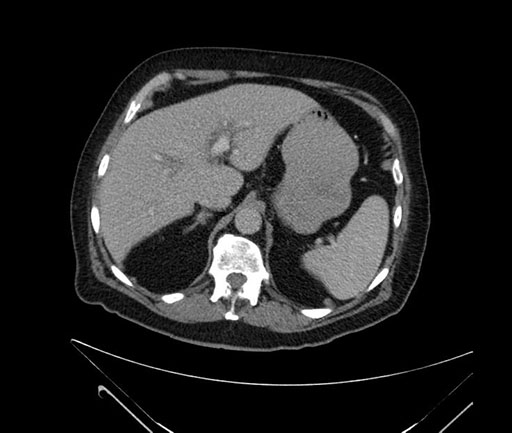

Whipple (pancreaticoduodenectomy) [case 7]

Axial - stented